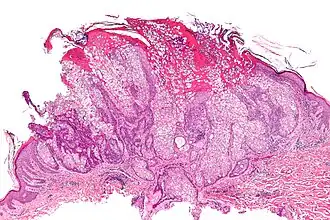

- d'atteintes dermatologiques : lésions à type d’adénome sébacé, de kératoacanthome, de carcinome ou d'épithélioma sébacé ;